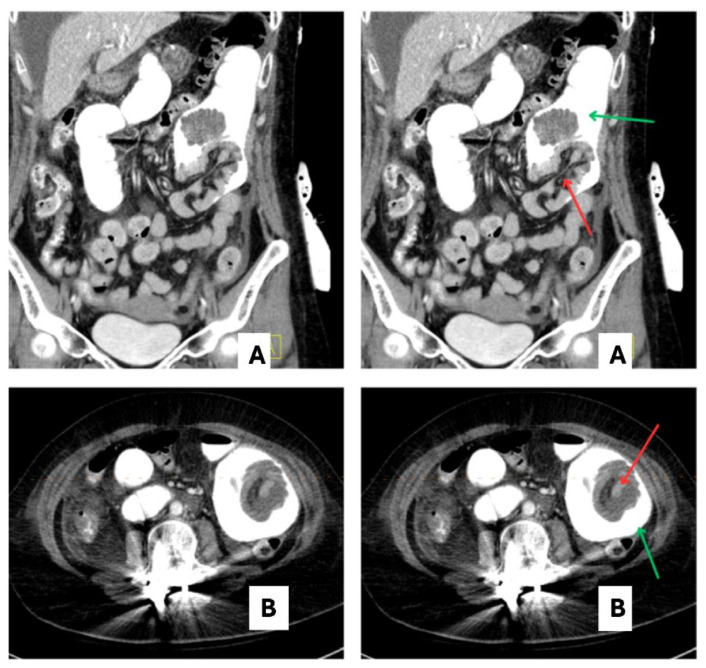

Bowel intussusception is rare in adults and accounts for less than 5 % of all cases, occurs in only 1 % of patients with bowel obstruction and in 0.64 % of patients following Roux-en-y bypass surgery with a female predominance. Our case underscores the unusual size and configuration of intussusception, wherein the distal segment telescopes into the proximal segment, defying the conventional presentation. Notably, the rarity of observing intussusception following Roux-en-Y gastric bypass surgery is also highlighted. It is important to be clinically vigilant and keep long term sequalae of bariatric surgery on the differential. A 56-year-old female with a remote history of Roux-en-Y gastric bypass surgery presented with epigastric pain radiating to the lower left and right quadrants, nausea, and vomiting of 1-day duration. She was on a prolonged outpatient course of non-steroidal anti-inflammatory drugs and steroids for pain management following recent orthopedic procedure. In the emergency department, she was afebrile, saturating well on two liters of oxygen, and normotensive with sinus tachycardia. Labs showed leukocytosis with mildly elevated lipase, alkaline phosphatase, and lactic acid. Initial CT abdomen pelvis with contrast was unremarkable. The patient continued to experience abdominal pain with worsening lactic acid. Repeat imaging revealed a 10 cm enteroenteric intussusception containing proximal jejunum with the gastric bypass Roux limb acting as the intussuscipiens. No obvious mass or lead point was identified. Ulceration/stricture at the jejunojejunal anastomosis was thought to be contributory to this. The patient underwent successful laparoscopic surgery.